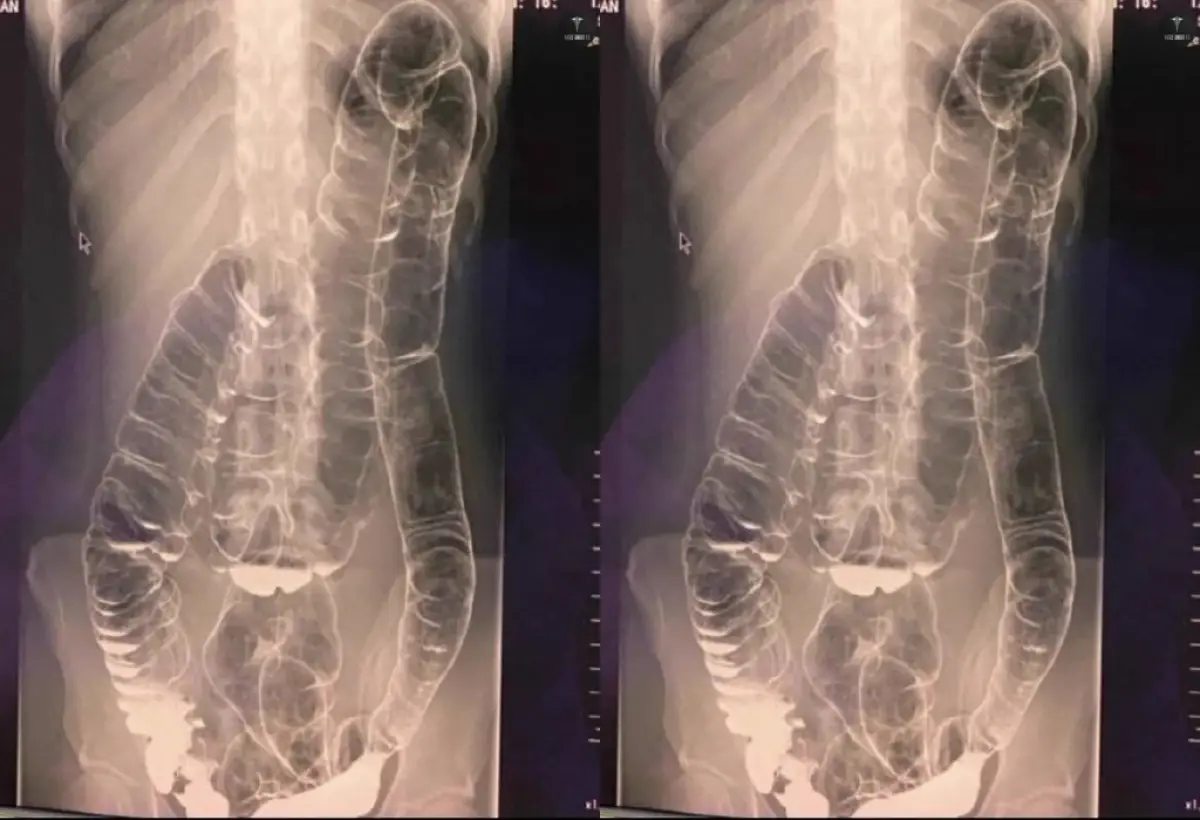

INFOSEMARANG.COM -- Jagad maya dihebohkan dengan beredarnya sebuah hasil foto rontgen seorang pasien yang sudah tidak BAB selama satu bulan.

Dalam foto rontgen yang beredar tersebut tampak bahwa usus besar pasien sudah naik ke bagian dada.

"Seorang pasien dengan keluhan tidak bisa BAB 1 bulan, apa yang kalian lihat dok? 😱" tulis akun @BaseAnakFK di X pada Rabu (27/9/2023).